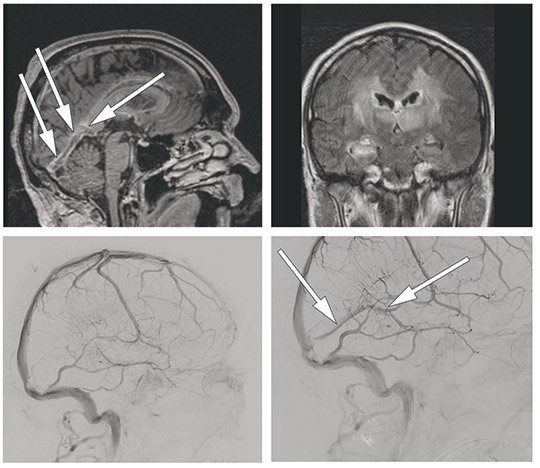

On cerebral contrast-enhanced and T1-weighted MRI (upper left), contrast sparing of the midline in the great cerebral vein (vein of Galen) and straight sinus (arrows) are shown. Bilateral signal changes on FLAIR are shown to the upper right, as a result of cerebral venous thrombosis.

Endovascular treatment was performed on a vital indication. Access to the intracranial venous system was obtained via a catheter from the right femoral vein to the right internal jugular vein. A microcatheter was advanced through the transverse sinus and sigmoid sinus to the straight sinus and the vein of Galen. After thromboaspiration and thrombectomy with a Solitaire temporary stent, the straight sinus and vein of Galen were recanalised. Cerebral angiography in venous phase (side view) after contrast injection in the left internal carotid artery is shown to the bottom left before the thrombectomy, and after to the bottom right. The arrows mark the open, above-mentioned venous structures after treatment.